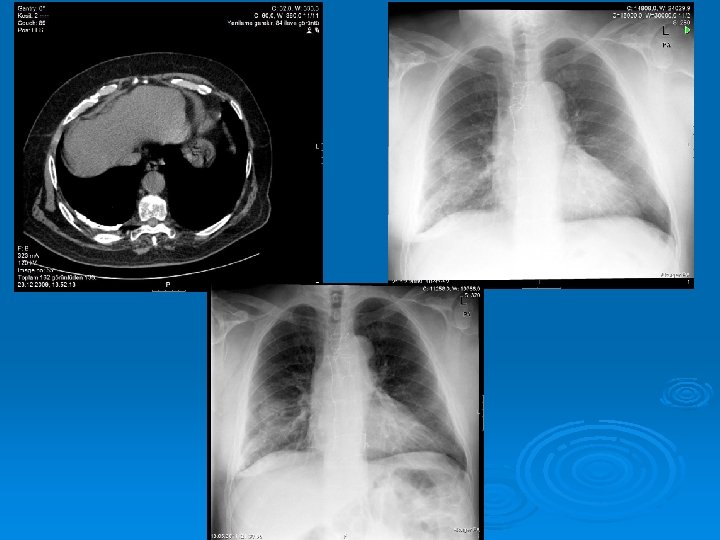

Radiology The fluid initially accumulates in the more dependent recesses of the thoracic cavity forming a Damoiseau Line Ø 200 -300 ml of pleural effusion can be detected on standard chest radiograph as blunting of the costophrenic angle Ø

Massive pleural fluid often shifts the mediastinum to the opposite side

Accumulation of the fluid between the diaphragm and the interior surface of the lung (Subpulmonic fluid): The hemidiaphragm appears to be elevated (Widening the distance between the top of the gastric bubble and the top of the left hemidiaphragm (>2 cm) and flatened Blunting of the posterior costophrenic angle on the lateral chest radiograph

Ø Smaller amounts of pleural fluid can be detected on lateral decubitus radiography as the free intrapleural fluid moves from top of the diaphragm to the dependent chest wall Pleural effusion in a lateral decubitus radiograph

Ø Ultrasound is able to demonstrate smaller amounts of fluid as 100 ml Ø CT has similar sensitivity to ultrasound, not routine but can be performed to evaluate concomitant paranchymal lesions Ø CT is sensitive in identifying pleural thickening and calcification